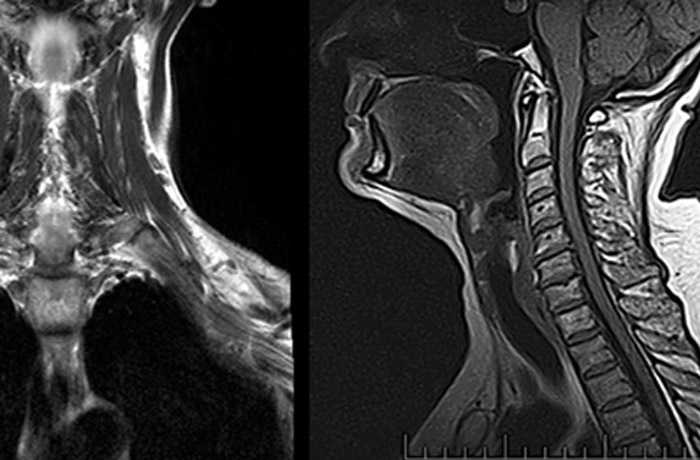

Компьютерная томография — диагностический метод, принцип которого основан на действии рентгеновского излучения.

Аппарат синтезирует рентгеновские лучи, которые проходят через исследуемую область тела пациента. Затем томограф анализирует полученные показатели. Каждая ткань или орган по-разному реагирует на излучение в силу особенностей строения и плотности. Итог работы компьютерного томографа – получение объемного изображение исследуемого органа.